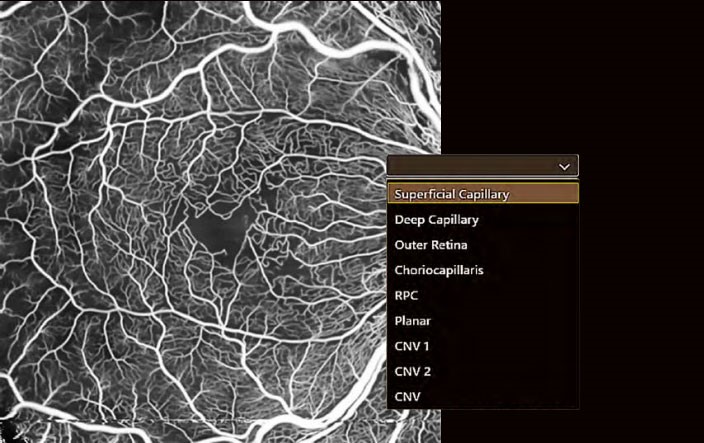

ВІЗУАЛІЗАЦІЯ МІКРОСУДИН СІТКІВКИ ЗА ДОПОМОГОЮ ОКТ АНГІОГРАФІЇ

ОКТ-ангіографія - це досконала технологія, яка виявляє рух еритроцитів у судинній сітці сітківки та дозволяє детально візуалізувати крихітні судини.

Неінвазивне дослідження з результатом через секунди.

ОКТ ангіографія не потребує введення флюоресцеїну або розширення зіниці, а обстеження займає лише кілька секунд. Відстеження сітківки у режимі реального часу за допомогою скануючого лазерного офтальмоскопа мінімізує артефакти. Найточніша обробка зображень з видаленням артефактів 3D проекцій забезпечує чудову якість зображення.

Вільне обирання шарів

За допомогою ОКТ ангіографії навіть найменші судини можна представити у 2D та 3D режимах.

Програмне забезпечення ОКТ Ангіо від Canon дозволяє вільно обирати шари для створення бажаного зображення.

Шари можна визначати на основі автоматичної сегментації або на власний вибір.